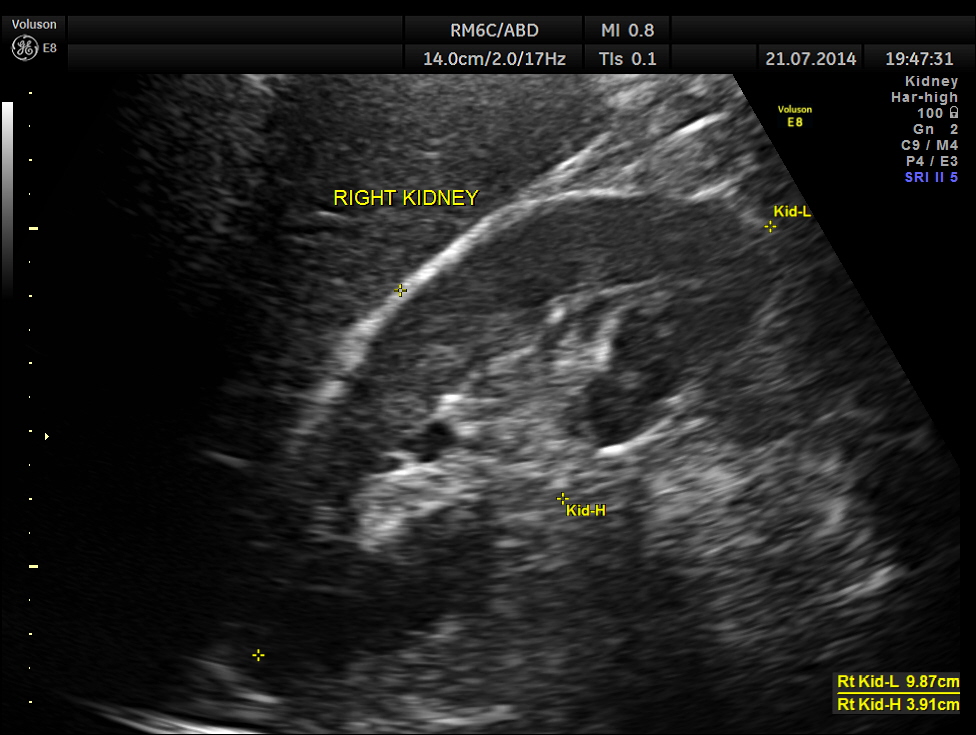

This was a 42-year-old gentleman , a known case of Insulin dependant Diabetes Mellitus. He was being evaluated by his physician for loss of weight and abdominal pain of a few months duration.

His abdominal ultrasound pictures are given below.